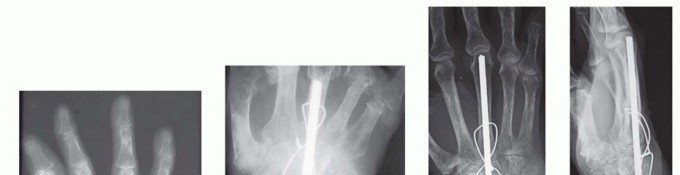

Joint Preparation and Decortication

The success of any arthrodesis is fundamentally dependent on the meticulous preparation of the articular surfaces. The goal is to completely eradicate all remaining hyaline cartilage and expose healthy, bleeding subchondral bone to facilitate robust osteogenesis. Using a combination of a #15 scalpel blade, sharp curettes of varying sizes, and small rongeurs, the surgeon systematically denudes the specific joints targeted for fusion. For a complete wrist arthrodesis utilizing a plate fixed to the third metacarpal, the requisite joints for decortication include the radioscaphoid, radiolunate, scaphocapitate, capitolunate, and the third carpometacarpal joint. While the triquetrolunate and other ulnar-sided joints may technically be left intact if asymptomatic, most surgeons prefer a pan-carpal decortication to maximize the total surface area available for the fusion mass.

Image

In areas of severe eburnation and subchondral sclerosis, manual curettage is often insufficient. A high-speed, water-cooled pneumatic burr (such as a 3mm matchstick or round burr) is utilized to meticulously remove the sclerotic bone down to a vascularized cancellous bed. Extreme care must be taken during burring to avoid thermal necrosis of the bone, hence the necessity of continuous, copious saline irrigation. To further stimulate the local osteogenic response, the denuded subchondral surfaces are repeatedly fenestrated or "shingled" using a 0.045-inch smooth Kirschner wire or a fine drill bit. This process opens the medullary canals of the carpal bones, allowing the influx of osteoprogenitor cells and marrow elements into the fusion site. If significant bone voids are present following decortication, cancellous autograft (typically harvested from the distal radius or iliac crest) or high-quality allograft must be packed tightly into the interstices to ensure structural continuity.